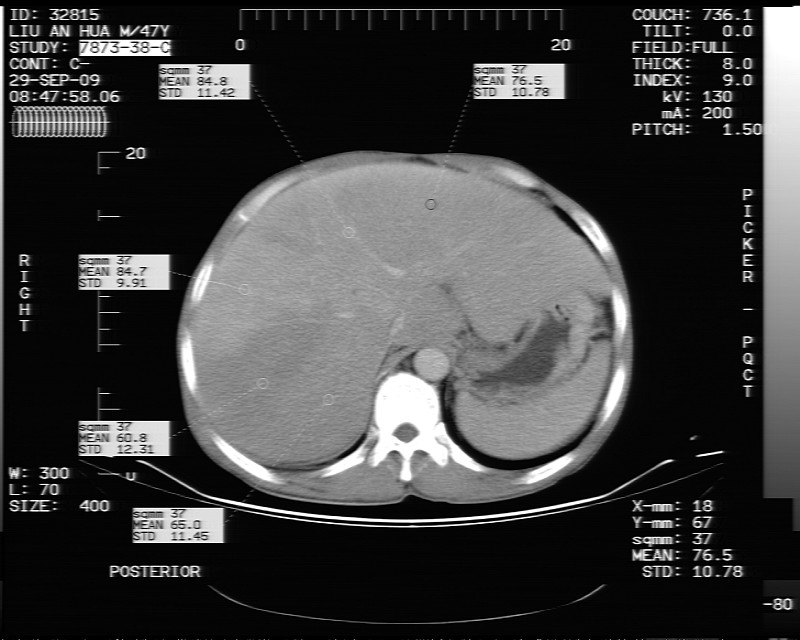

动态增强示:

支持脂肪肝【无占位性,高低密度区同期强化,平扫与强化的密度成比例】

不均匀性脂肪肝。肝脏体积稍大,不除外合并肝功能损害。

1.脂肪肝;

2.右肾结石。

1、不均匀脂肪肝;2、布加氏综合症(肝脏肿大,门脉纤细,下腔海绵状变性,肠系膜上静脉显著扩张)。